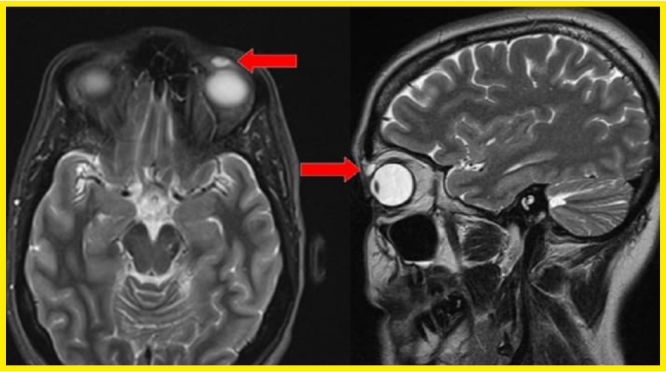

Na rentgenovém snímku byla vidět jakousi cysta, která však byla při operaci velkým překvapením. Po odstranění cysty našli v oku i prasklou kontaktní čočku. Objektiv byl starší typ objektivu vyrobený z mnohem tvrdšího materiálu. Na rozdíl od měkkých kontaktních čoček, které se dnes většinou používají, jsou čočky RGP starším typem, které byly poprvé použity v 60. letech 20. století. Jsou těžší než moderní čočky, což znamená, že mohou být zpočátku nepohodlné. Navíc mohou samovolně vypadnout z oka.

Lékaři tedy po dlouhých 28 letech zjistili, že čočka byla v oku ženy. Tento typ čoček měla pacientka naposledy ve 14 letech. Po tom drobném poranění oka při sportu si všichni mysleli, že čočka z oka prostě vypadla, ale nikoho by ani nenapadlo, že v oku zůstala.

"Můžeme odvodit, že čočka RGP migrovala do pacientova levého horního víčka v době traumatu a byla in situ posledních 28 let," napsal Dr. Sirjhun Patel z oftalmologického oddělení na University of Dundee v Dundee, Spojené království.